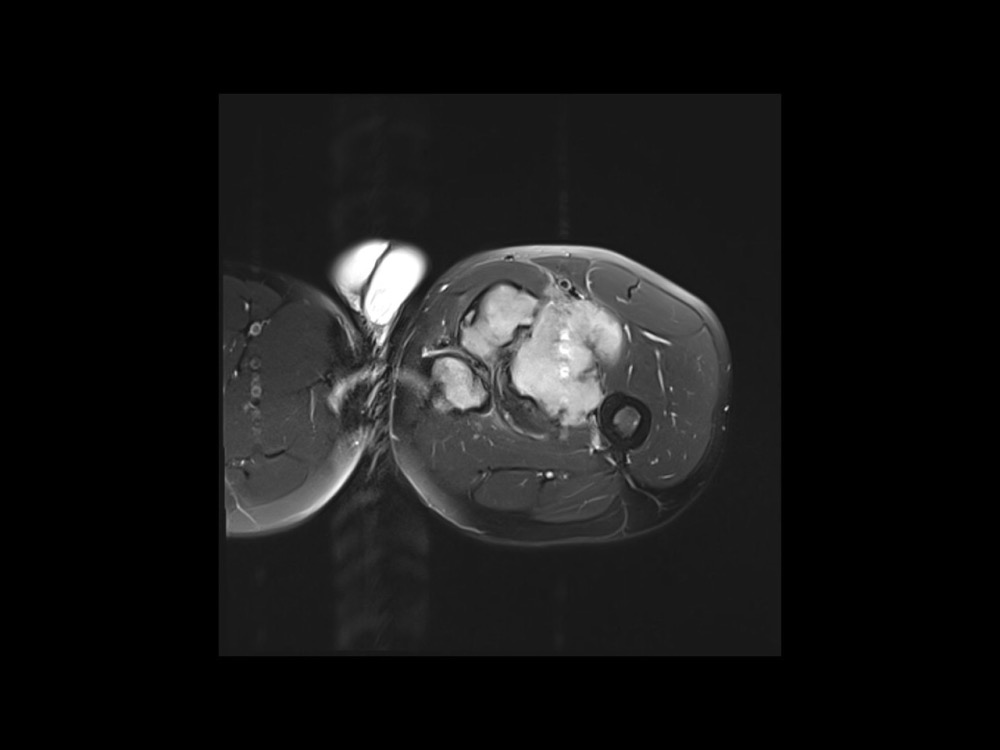

Moalla / Mihoubi-Bouvier / Drapé 18/05/2022